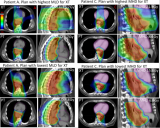

欧洲多中心食管癌III期随机对照临床试验比较质子与光子治疗计划的鲁棒性

欧洲随机III期PROTECT试验比较了八个癌症中心质子与光子治疗食道癌的剂量分布和治疗计划的鲁棒性。所有中心使用4DCT扫描对4例接受28次50.4 Gy (RBE)的患者均分别进行一项优化PT和一项优化XT的计划。以超过99%靶区容积能接受到95%计划剂量(V95%iCTVtotal)评估治疗方法对摆位、射程和呼吸的鲁棒性。 2022-06-21 核医学质子治疗